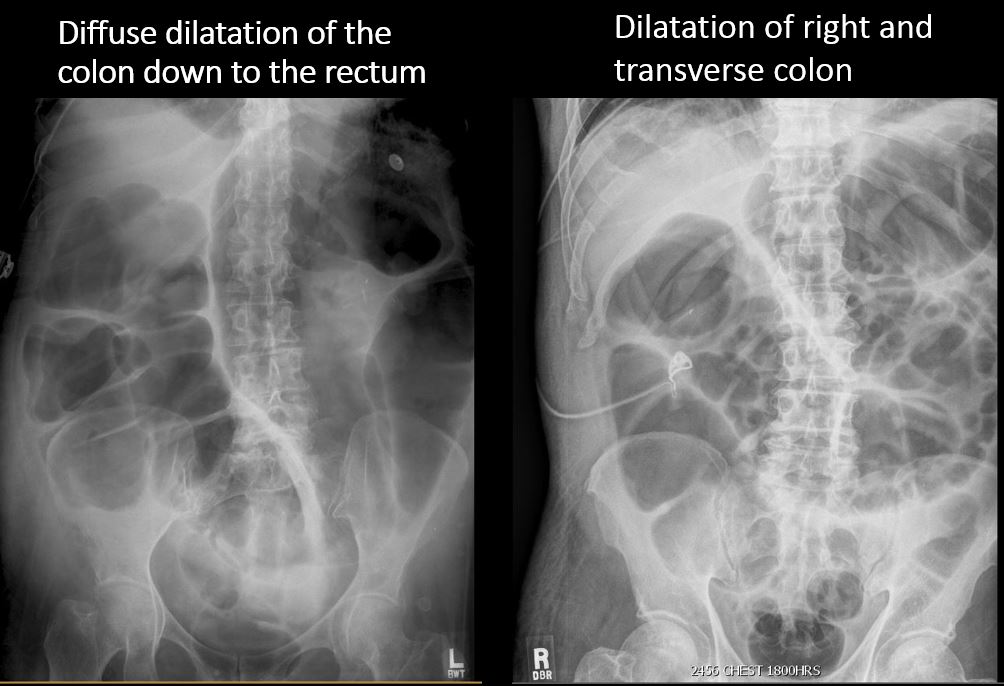

A segment of colon is distended or dilated with decompression of the more distal colon. [Yes/No]

There is dilatation of the ascending, transverse, descending, and/or sigmoid colon measuring over 6 cm. [Yes/No]